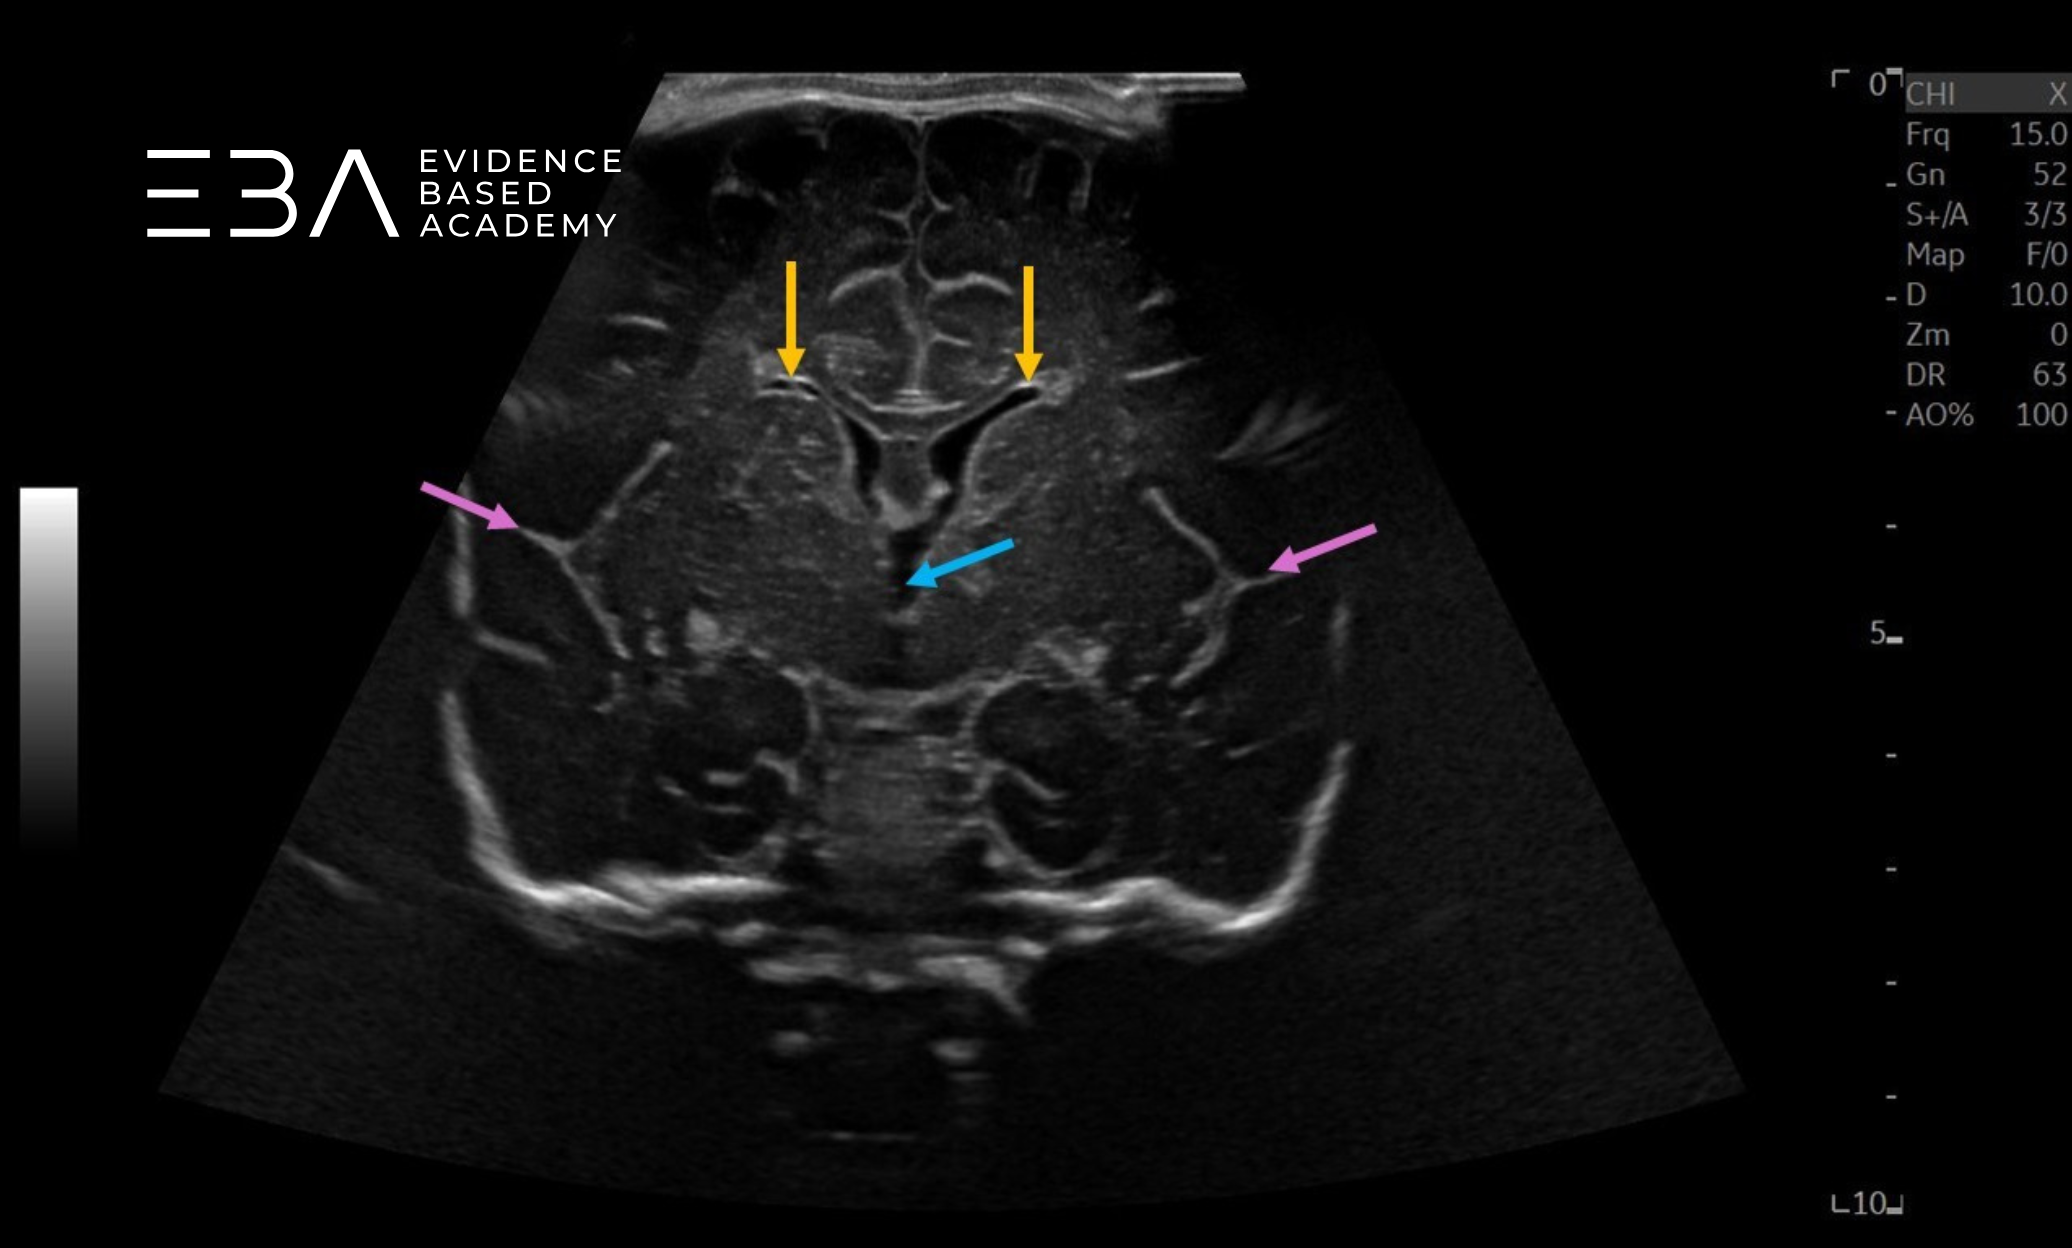

zdj. 12

Głowica liniowa. Rogi czołowe komór bocznych (żółte strzałki), komora trzecia (niebieska strzałka), bruzdy boczne / szczeliny Sylwiusze (fioletowe strzałki).

Projekcja 3 – na poziomie wzgórza: widoczne są bruzdy boczne, strop komory trzeciej i płaty skroniowe. Jądra ogoniaste tworzą ściany boczne układu komorowego, ciało modzelowate — strop, a przegroda przezroczysta – ścianę przyśrodkową. Komora trzecia jest cienką bezechową strukturą pośrodkową między wzgórzami. Poniżej leżą struktury pnia mózgu (3, 6).